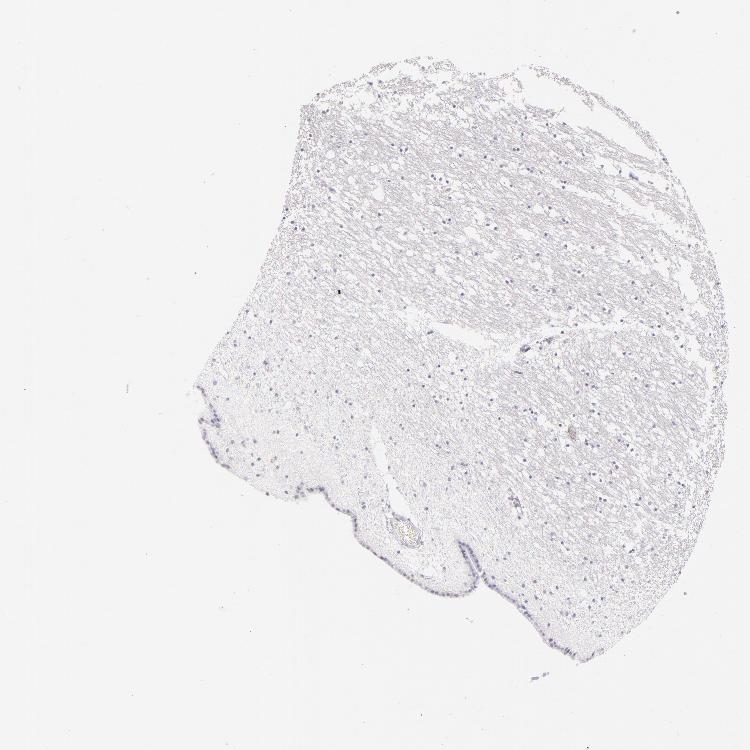

CAUDATE - Antibody stainingi

Antibody staining in the annotated cell types in the current human tissue is reported as not detected, low, medium, or high, based on conventional immunohistochemistry profiling in selected tissues. This score is based on the combination of the staining intensity and fraction of stained cells.

Each image is clickable and will lead to virtual microscopy that enables deeper exploration of all samples and also displays staining intensity scores, fraction scores and subcellular localization as well as patient and tissue information for each sample.

Antibody HPA011157Antibody CAB002223Antibody CAB012978Antibody CAB079960

Glial cells Not detectedNot detectedNot detectedNot detected

Neuronal cells LowNot detectedNot detectedNot detected